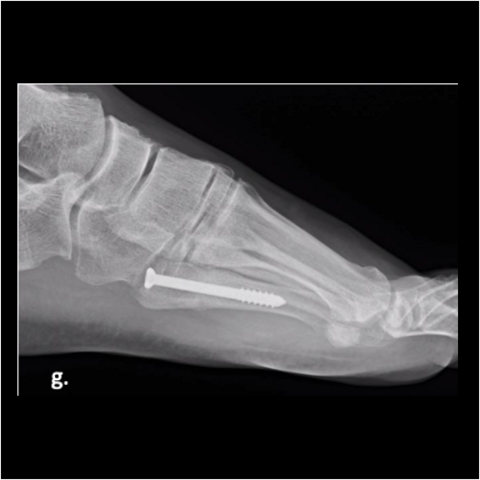

Figure 2g

Figure 2g. Here is the 30-year-old soldier’s foot 3 months post-injury.